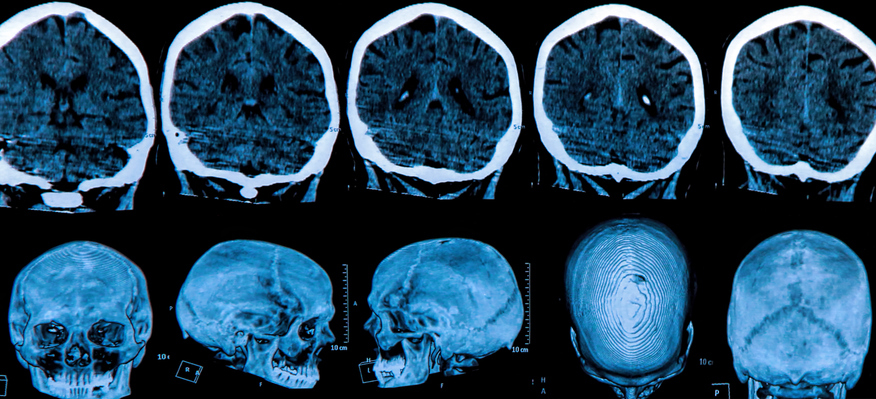

One of the most challenging and mysterious things about Alzheimer’s disease is predicting when and whether it will strike. Alzheimer’s detection has benefited from the discovery of a number of genetic markers, but there is still much to be done in Alzheimer’s disease research.

Recently, a massive international effort was launched to synthesize all the latest genetic data into a complete Alzheimer’s screening. This one test, administered through genome screening, is the most comprehensive approach available for evaluating Alzheimer’s risk.

The Polygenic Hazard Score Test uses data from 31 separate genetic markers to reach conclusions about an individual’s likelihood of developing Alzheimer’s in the future. The test also provides information for those with a low-risk genetic profile.

The new test was derived from long-term study of more than 70,000 individuals, including both current Alzheimer’s patients and healthy older people. It began with nearly 2,000 minute genetic differences before zooming in on the current set of just a few dozen.

By focusing on these specific differences, experts now have the ability to predict a person’s odds of developing Alzheimer’s in any given year. Preventive care – as well as enrichment aimed at increasing quality of life – can begin early in the at-risk populations.